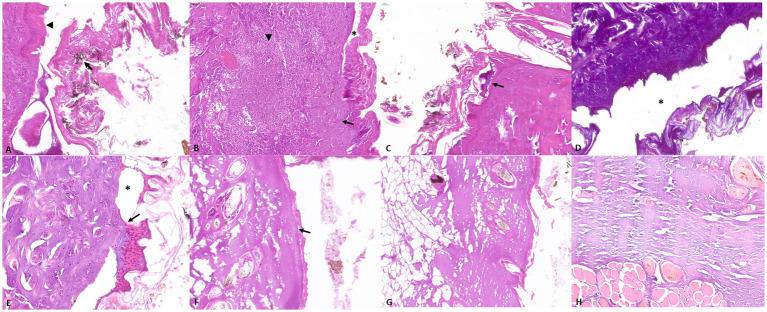

Fire-related deaths are usually a consequence of carbon monoxide (CO) poisoning or shock from thermal injuries. In humans, high levels of carboxyhemoglobin (COHb) concentrations in the blood can support a diagnosis of CO poisoning. In veterinary medicine, few studies investigated the pathological changes and blood COHb% in fire victims, and no data are available on post-mortem changes in blood gas composition due to fire. This study aims to investigate the pathological changes and COHb levels in both animal victims of fire and cadavers experimentally exposed to fire. For this purpose, dogs were selected and subdivided into three groups. Group A comprised 9 adult dogs, and Group B comprised 7 puppies that died under fire-related conditions. Group C was represented by 4 dog cadavers experimentally exposed to heat and smoke. A complete macroscopic, histological, and COHb evaluation were performed on each animal. Animals in Groups A and B showed cherry-red discoloration, thermal-injuries and soot deposits along the respiratory tract. Animals in Group C showed thermal injuries and soot deposits limited to the upper respiratory tract. The mean COHb% values in cadavers in Group C were lower than those observed in the other groups but higher compared to the values detected before the heat and smoke treatment. These findings suggest that both pathological changes and COHb analysis are valid tools for investigating fire-related deaths in dogs. However, the increase of COHb levels in cadavers exposed post-mortem to heat and smoke highlights how the COHb analysis should always be evaluated together with macroscopical and microscopical findings to avoid significant misjudgments in investigating fire-related fatalities in veterinary forensic practice.

与火灾相关的死亡通常是一氧化碳(CO)中毒或热损伤休克的结果。在人类中,血液中高浓度的碳氧血红蛋白(COHb)可支持一氧化碳中毒的诊断。在兽医学中,很少有研究调查火灾受害者的病理变化和血液中COHb%,也没有关于火灾导致的死后血气成分变化的数据。本研究旨在调查火灾动物受害者和实验性暴露于火灾的尸体的病理变化和COHb水平。为此,选择了狗并将其分为三组。A组包括9只成年狗,B组包括7只在与火灾相关的条件下死亡的幼犬。C组由4只实验性暴露于热和烟雾的狗尸体组成。对每只动物进行了完整的宏观、组织学和COHb评估。A组和B组的动物表现出樱桃红色变色、热损伤以及呼吸道有煤烟沉积。C组的动物热损伤和煤烟沉积仅限于上呼吸道。C组尸体的平均COHb%值低于其他组,但高于热和烟雾处理前检测到的值。这些发现表明,病理变化和COHb分析都是调查狗与火灾相关死亡的有效工具。然而,死后暴露于热和烟雾的尸体中COHb水平的升高凸显了在兽医法医实践中调查与火灾相关的死亡时,COHb分析应始终与宏观和微观发现一起评估,以避免重大误判。